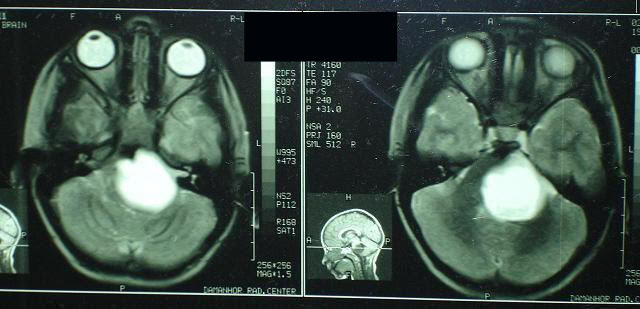

هذا مثال لحالة أصابهاا حول شللي

بالعصب السادس بالعين اليسرى و بالفحص بالرنين

المغناطيسي للمخ تبين أنه يوجد ورم بالمخ .يرى صورة

عين الحالة لاتستطيع الاتجاه لليسار و يرى صورة الحالة

بعد جراحة الورم بواسطة جراح المخ و الأعصاب و بعد

جراحة العين